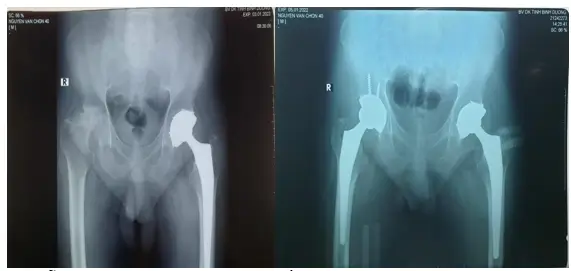

Phẫu thuật thay khớp háng toàn phần phải, trái cho Bệnh nhân hoại tử chỏm xương đùi 2 bên